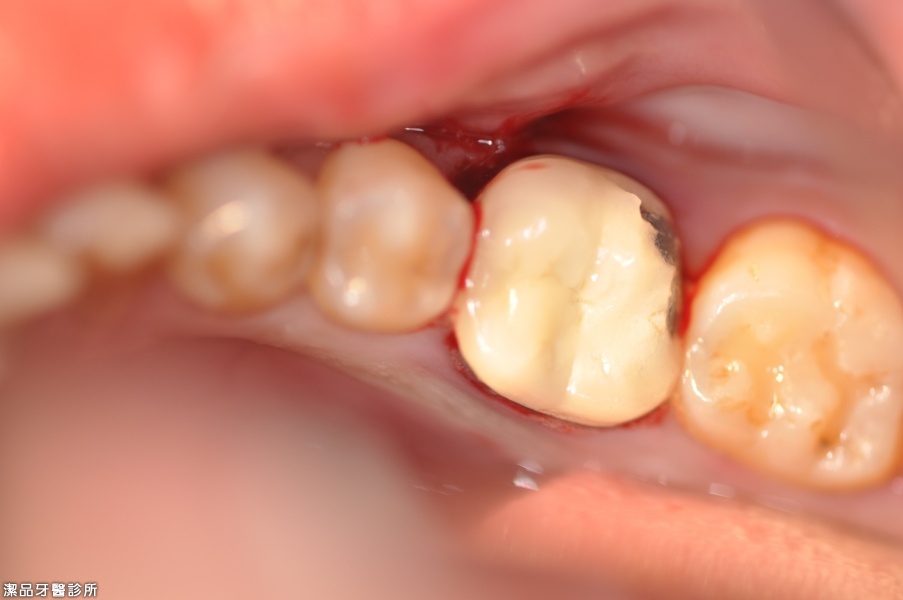

牙根嚴重發炎